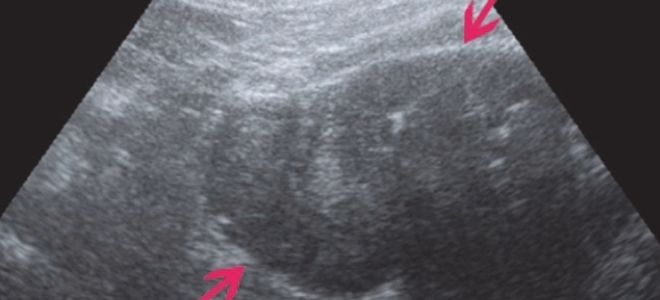

Эхопризнаки микролитиаза

Для выявления микролитов в почках применяются различные инструментальные методы исследования. Основным методом диагностики микролитиаза является ультразвуковое исследование (УЗИ). Во время процедуры на экране аппарата специалист может заметить мелкие песчинки, расположенные в лоханках почки. При этом сам орган может быть увеличен и отечен. В некоторых случаях также могут быть выявлены одиночные небольшие конкременты.

Важно отметить, что соли оксалатов плохо отображаются на УЗИ: их можно увидеть только в том случае, если размер образований превышает 6 мм. Поэтому для окончательной диагностики микролитов в почках, о которых говорилось ранее, ультразвуковое исследование обычно дополняется урографией.